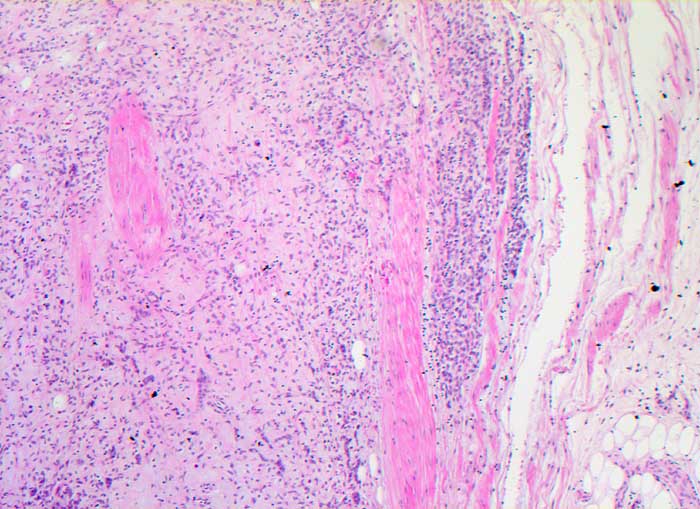

PathoPic ID 5936 - Myxoid/rundzelliges Liposarkom

Myxoid/rundzelliges Liposarkom

maligner Tumor

Weichteile Bein

Weichteile

Invasion der

Faszie durch einen rundzelligen unscharf begrenzten unterschiedlich zelldichten Tumor.

Weichteiltumor Oberschenkel medial.

Histologie

50